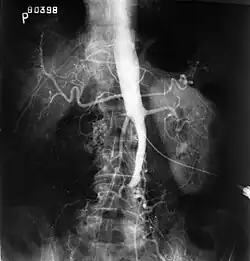

| Plate from Gray's Anatomy showing the abdominal aorta and the common iliac arteries | |

The physical examination usually shows weakened femoral pulses and a reduced ankle-brachial index. The diagnosis can be verified by color duplex scanning, which reveals either a peak systolic velocity ratio ≥2.5 at the site of stenosis and/or a monophasic waveform. MRA and multidetector CTA are often used to determine the extent and type of obstruction. Another technique is digital subtraction angiography which allows verification of the diagnosis and endovascular treatment in a single session.[2]

Angiography provides important information regarding the perfusion and patency of distal arteries (e.g. femoral artery). The presence of collateral arteries in the pelvic and groin area is important in maintaining crucial blood flow and lower limb viability. However, angiography should only be used if symptoms warrant surgical intervention.[2]